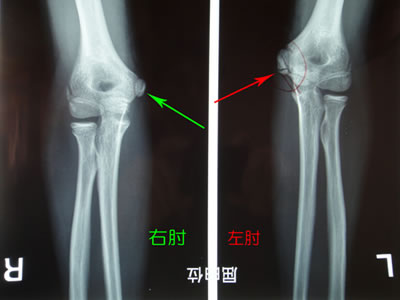

伸展位での画像(↓):右肘(健側) 左肘(患側)

屈曲位撮影と比較して、赤矢印の先にある黒い線がわかりにくくなっています。

同じ選手の後方レントゲン画像(↓)です。:右肘(健側) 左肘(患側)

左肘赤矢印先が二分しています。

後方の骨端核は、個人差や左右差が大きいので比較時には注意が必要です。